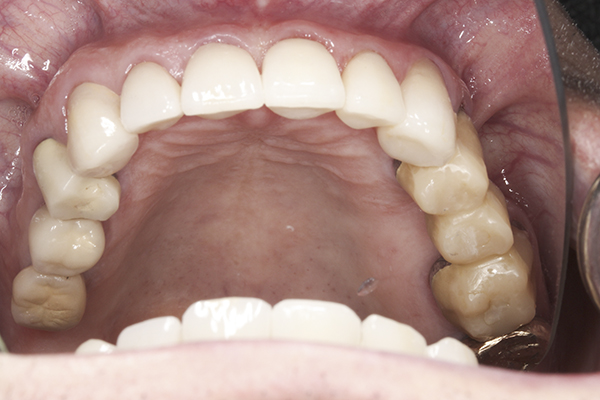

(15.) Preoperative maxillary, occlusal view.

Figure 15

(41.) Postoperative maxillary occlusal view. Note the composite tops on teeth Nos. 12 through 14.

Figure 41